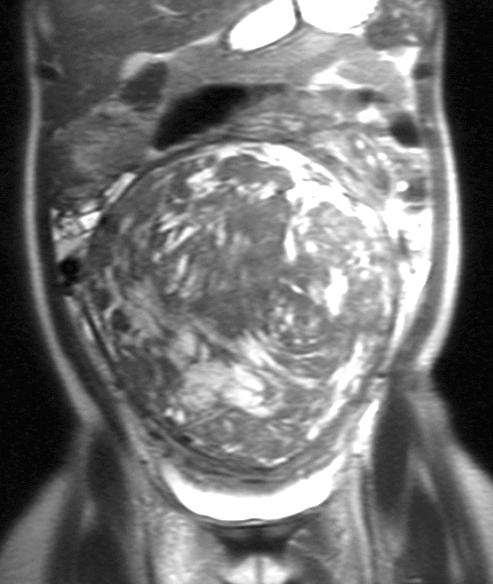

40 yold, G0 P0;MRI,较大间质内子宫肌瘤。月经稍多,肿块症状,逐渐长大。从未成功受孕;子宫肌瘤被认为是主要原因;目前不希望怀孕。因为肌瘤切除困难,妇科医生建议子宫切除。

![]() |

| 2003/03 | 2003/03 |